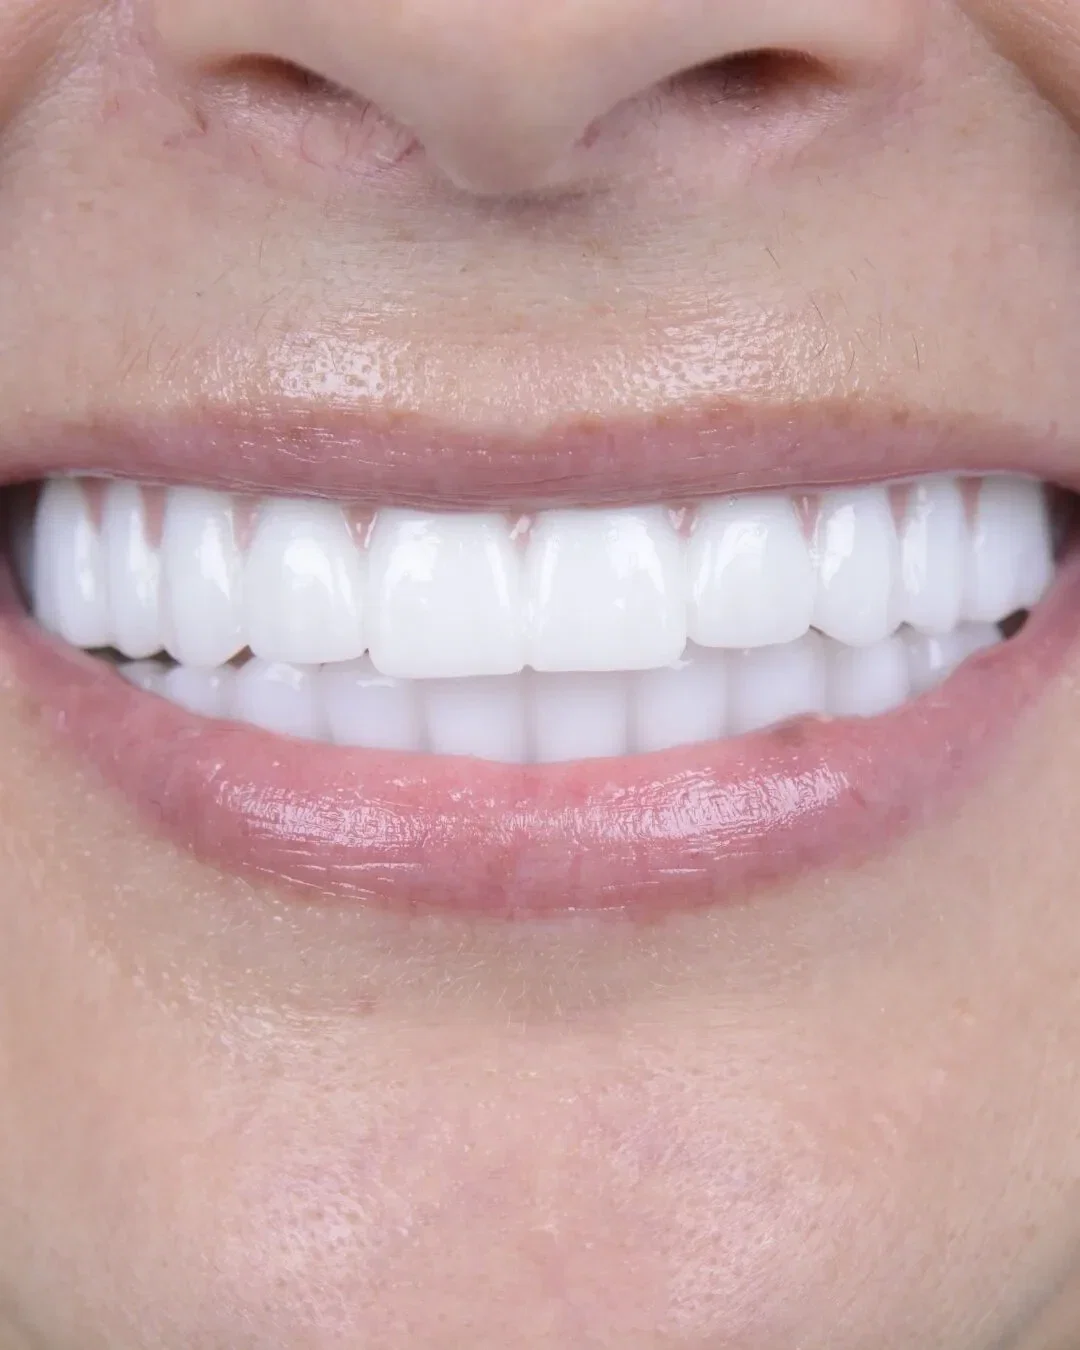

Real Smile Transformations

See the life-changing results from real patients who chose Fusion Dental Implants.